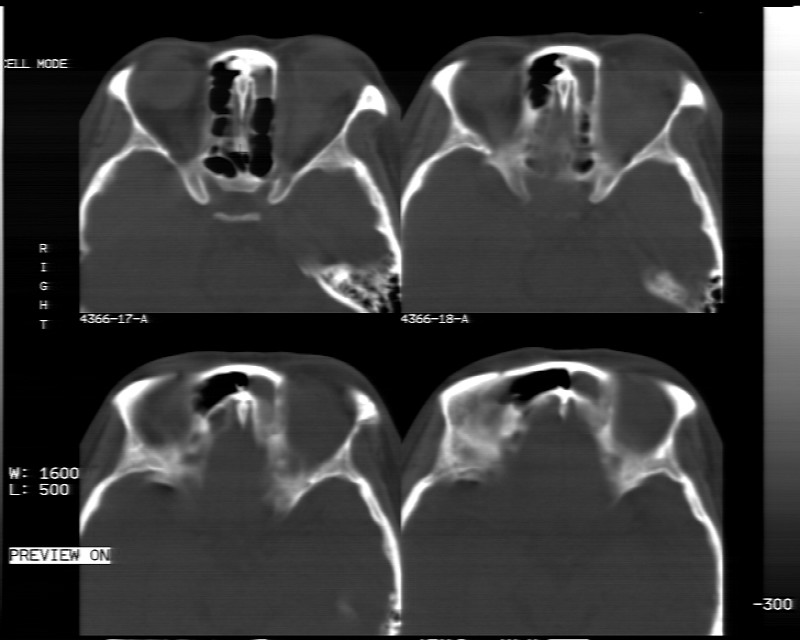

女性,40岁,左眼疼痛,视力模糊,五年曾行左眼脂肪瘤手术。

患者现病史不知持续有多久了,现片示眶内病灶边缘较模糊,眶脂混浊,多考虑炎性假瘤,不除外肿瘤

1)左眼眶内占位性病变,性质待定(不排除炎性假瘤);建议行进一步检查。2)左侧额窦炎。